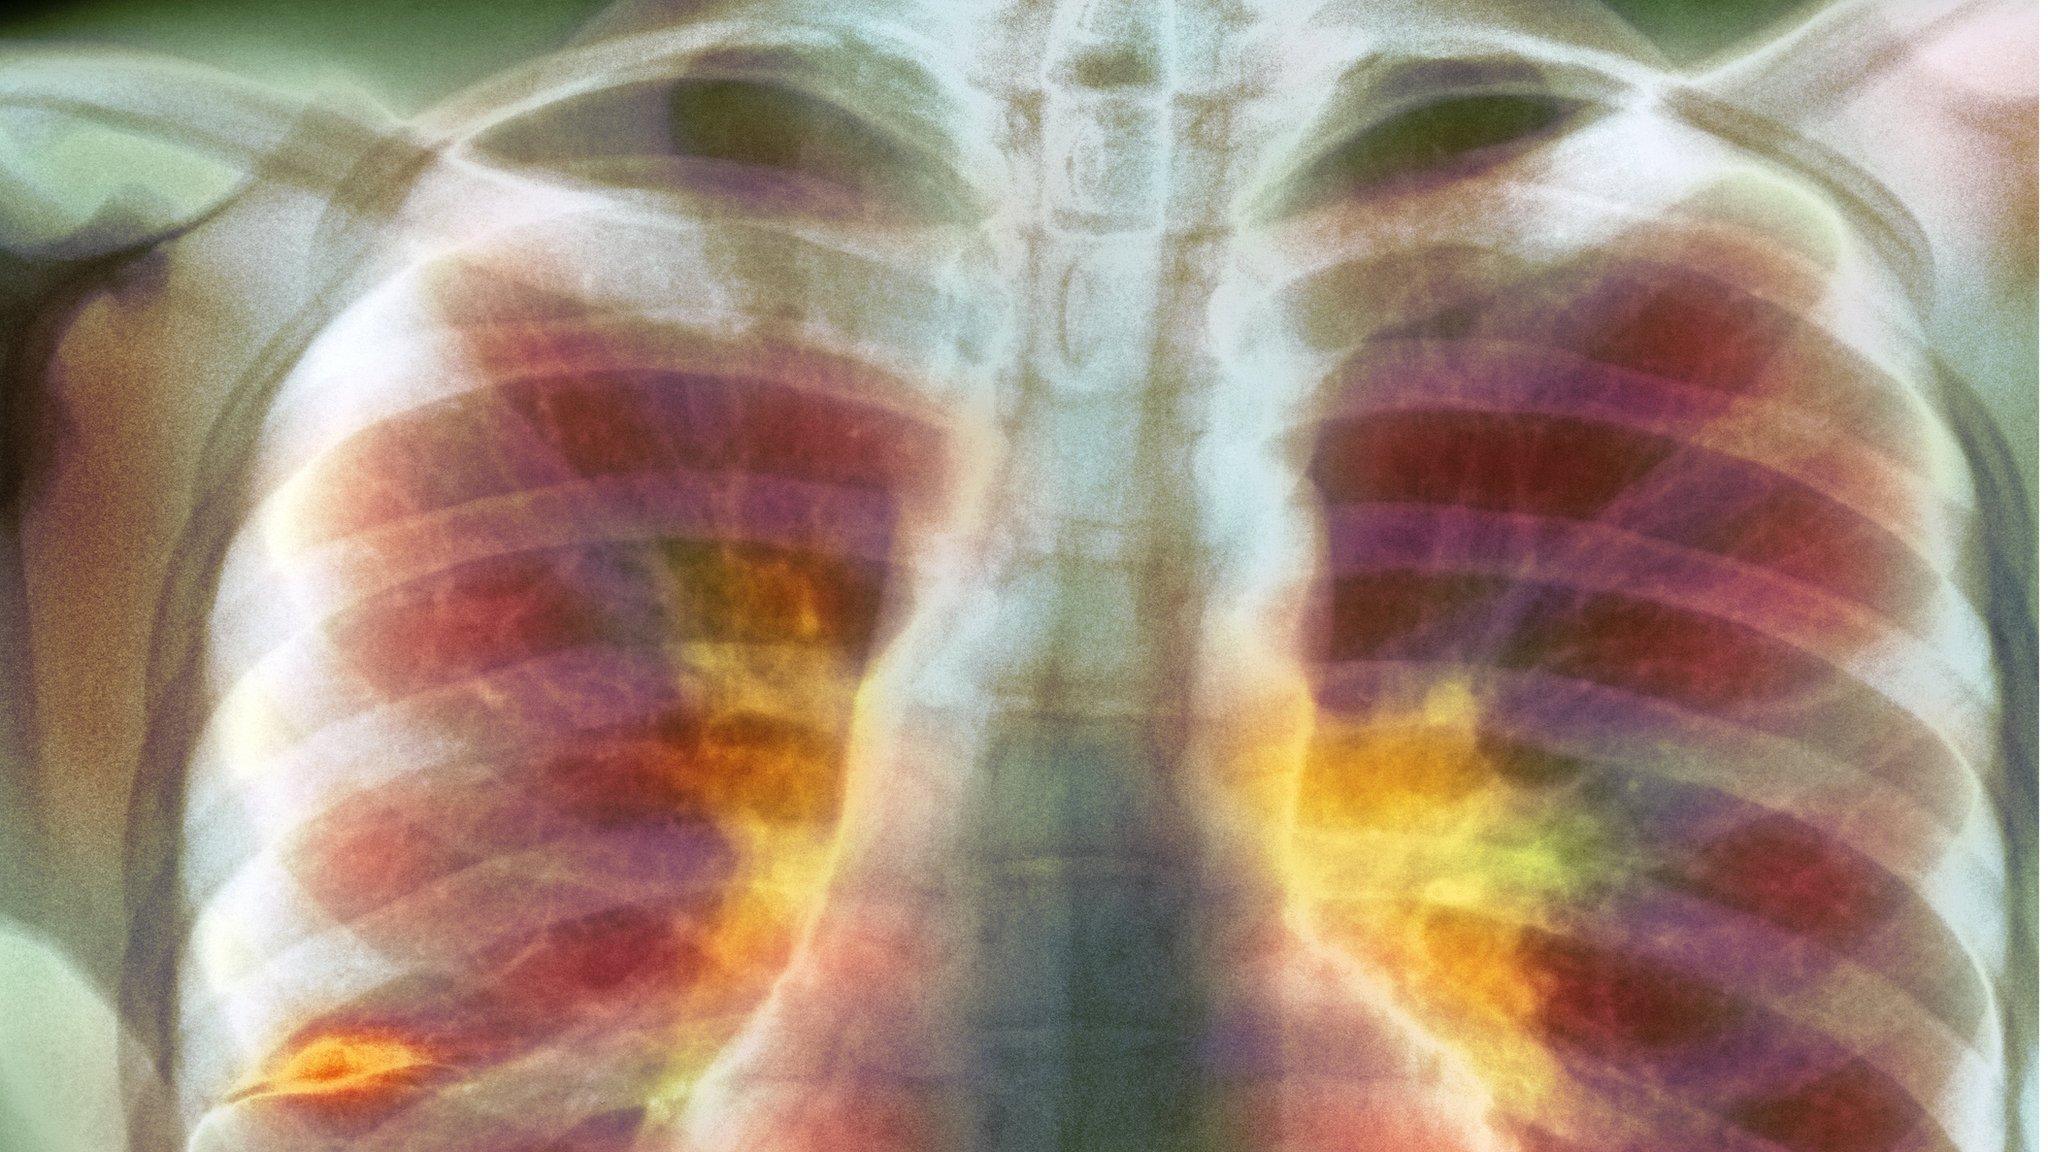

More than 650,000 children worldwide develop tuberculosis each year, research in the journal Lancet Global Health suggests.

Tuberculosis (TB) in children can be difficult to detect - younger people harbour fewer bacteria than adults and it is more challenging to collect samples from them.